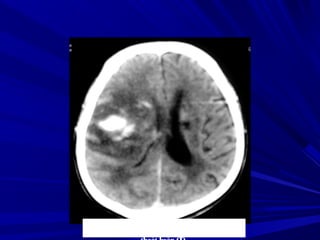

Buøi vaên L., Nam, 45 tuoåi, Xuaát huyeát nhaân beøo-bao trong (P) coù

traøn maùu naõo thaát